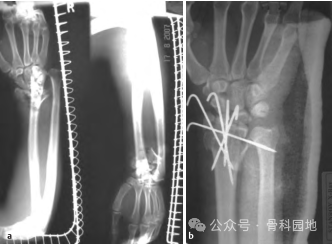

13、应用外固定架治疗桡骨远端粉碎性骨折,外固定架适用于严重粉碎性桡骨远端骨折,伴有巨大肿胀、开放骨折,或局部皮肤状况不允许进行内固定(例如钢板固定)(下图a-d)。